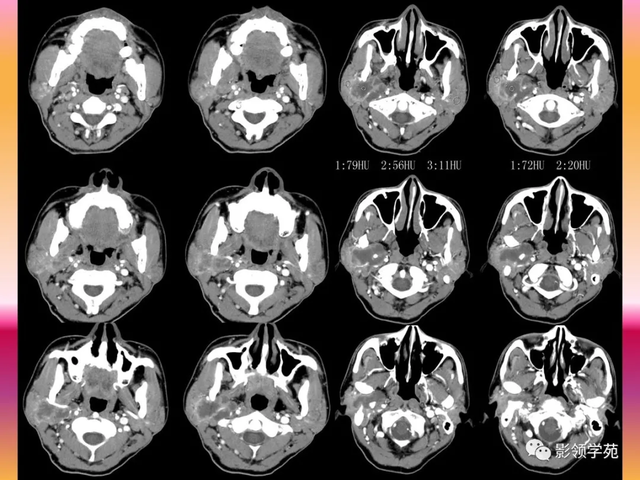

良性腮腺肿瘤的CT体现:

圆形或椭圆形;

可有分叶,边缘多清晰 ;

等密度或稍高密度,CT值30-60HU

增强轻中度均质性强化;

可有囊变,点状、条状或小斑片状钙化

钙化主要见于良性混淆瘤及神经鞘膜瘤